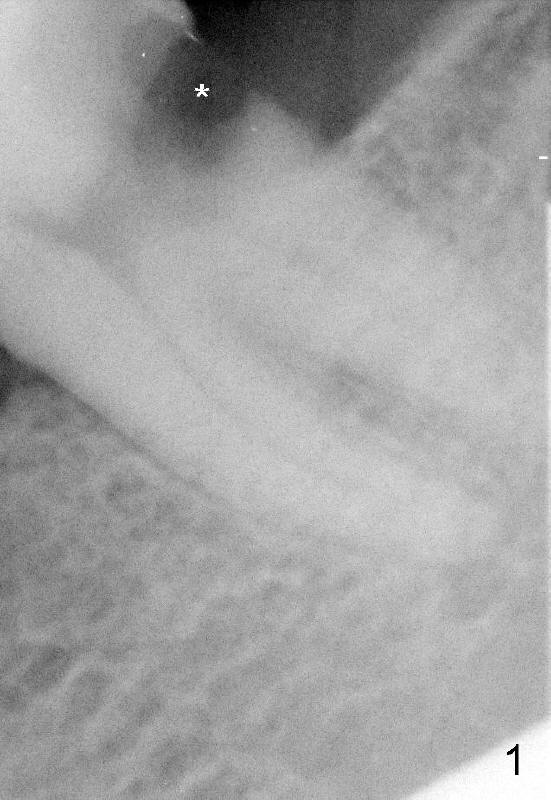

五十六岁唐女士因为在别的诊所治疗不顺利又回到本诊所来,需要做多个植牙,迫切问题是左下七远中龋齿(图一*),牙齿疼痛,松动,有的医生认为救不了。综合考虑还是应该保留这颗磨牙,病人听了很高兴,我们开始根管治疗,但愿再次赢得病人信任。

图一表明这颗磨牙有两个分开的根,不像是C型根管,应该有三个根管:近中两个,远中一个。术中发现近中根管口是椭圆形,但是好像只能找到近中颊侧根管,近中舌侧根管老是找不到,根管治疗效果必定不好,挺难与病人交代,又可能失去这位病号,急着象热锅上蚂蚁。她拍摄过颌骨CT,但是那天她没有带来。